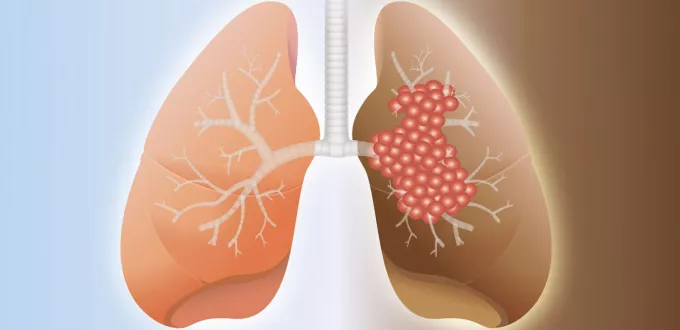

تليف الرئة هو حالة مزمنة تتميز بتندب وتغلظ أنسجة الرئة، مما يعيق وظائفها ويقلل من قدرة الجسم على الحصول على الأكسجين. على الرغم من عدم وجود علاج شافٍ تمامًا لتليف الرئة، إلا أن هناك العديد من الطرق التي يمكن أن تساعد في إدارة الأعراض وتحسين نوعية حياة المرضى.

تشمل هذه الطرق العلاجات الطبية التقليدية، بالإضافة إلى بعض العلاجات العشبية التي قد توفر بعض الراحة. يهدف هذا المقال إلى استكشاف الخيارات العلاجية المختلفة لتليف الرئة، مع التركيز على دور الأعشاب و العلاجات الطبية الحديثة.